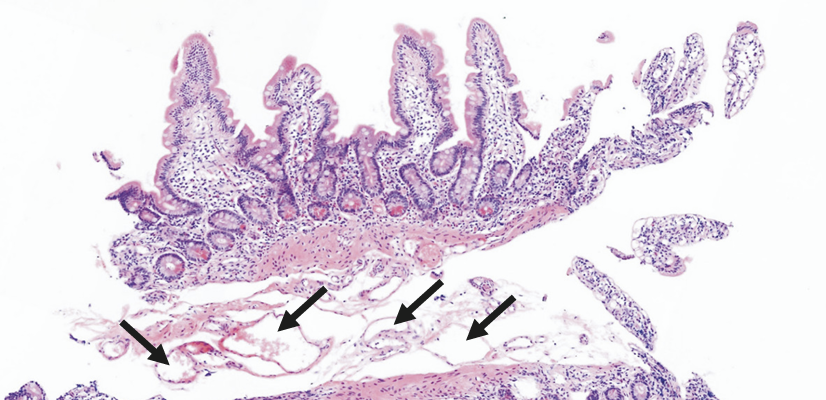

Endoscopy is the confirmative diagnostic approach for intestinal lymphangiectasia. Pathology of the affected mucosa demonstrates multiple dilated lacteals.